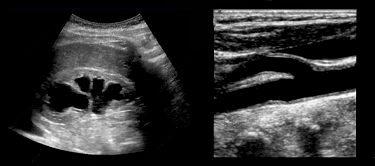

Ultrasound can feel intimidating at first. The images are unfamiliar, the controls seem endless, and many teaching environments assume prior knowledge that newer learners simply haven’t had the chance to build yet. We do things differently.

You’ll learn how to hold the probe with purpose, orient yourself confidently within anatomy, and recognize normal structures before pathologic ones are ever introduced. Doppler is taught as part of this same continuum—not as an advanced add-on, but as a natural extension of understanding motion, flow, and physiology at the bedside.

Nearly every minute of the course is devoted to guided, hands-on scanning. Short, clear teaching segments connect anatomy, physics, and instrumentation directly to what your hands are doing on the patient. You are never left wondering why something looks the way it does—or how to reproduce it again later

This foundational course matters because it teaches you how to see—not just where to place a probe. By combining guided bedside scanning with focused clinical reasoning, you’ll move from memorizing textbook images to understanding how anatomical motion, physiology, and patient context inform decision-making. If your goal is to make ultrasound a reliable extension of your clinical exam, this course gives you the skills to do it confidently and consistently.